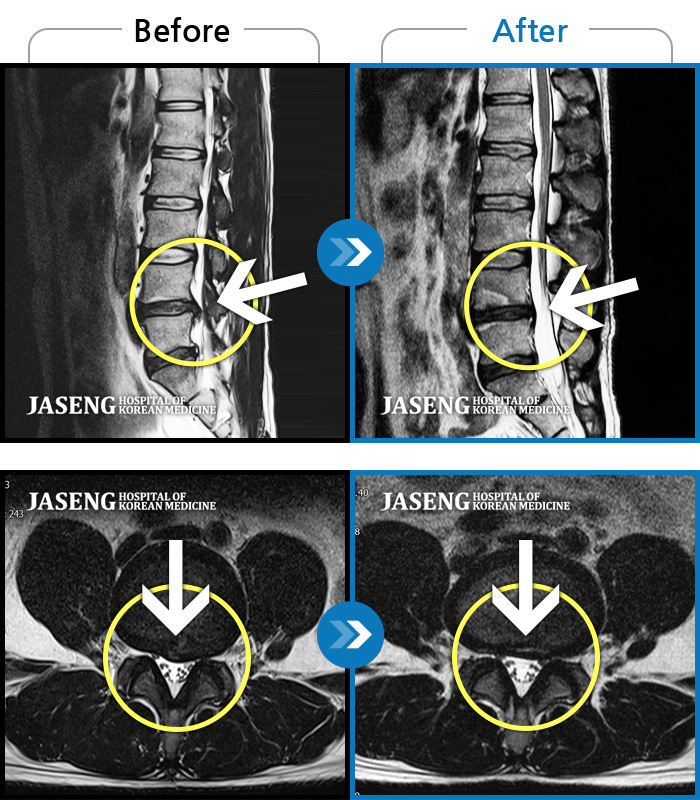

허리디스크

인천 · 조남훈 원장

좌측 허벅지와 종아리가 찌릿하고 묵직한 통증이 있어요.

촬영시기

2025.03.18 ~ 2025.07.22

2025.08.01